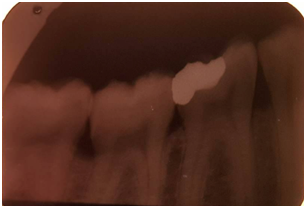

Gross excess resin can be removed after a spot cure, prior to completely curing the resin. Light curing is then done in accordance with the resin manufacturer’s recommendations. Any residual flash can be removed with a scalpel or suitable curette, but care must be taken not to cause inadvertent deficiencies at the tooth restoration interface.2,7 after which the occlusion is evaluated and adjusted as necessary. Any adjusted surfaces can be polished with a suitable polishing system, such as diamond polishing paste or rubber points (Figure 14 & Figure 15).7

Figure 14 Periapical view after bonding.